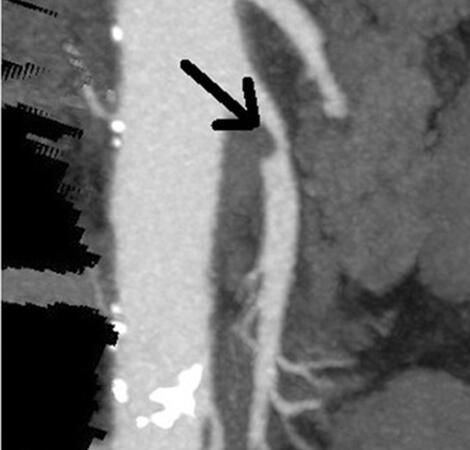

Η στένωση της μεσεντέριου αρτηρίας αναφέρεται στη στενωτική νόσο των αρτηριών που τροφοδοτούν το μεσεντέριο, ένα μεγάλο αγγείο που μεταφέρει το αίμα από την καρδιά προς τα άνω και κάτω άκρα. Η στένωση αυτή συνήθως οφείλεται στην αθηροσκλήρωση, μια κατάσταση όπου οι αρτηρίες συσσωρεύουν αστική ουσία, λίπη, και άλλα υλικά που σχηματίζουν αθηρώματα.

Η αθηροσκλήρωση μπορεί να οδηγήσει σε στένωση των αρτηριών, περιορίζοντας τη ροή του αίματος προς τα όργα που τροφοδοτούν. Στην περίπτωση της μεσεντέριου αρτηρίας, αυτό μπορεί να έχει επιπτώσεις στην καλή παροχή αίματος προς τον εγκέφαλο και τα άνω άκρα. Η σοβαρότητα της κατάστασης εξαρτάται από το βαθμό της στένωσης και τον τρόπο με τον οποίο επηρεάζει τη ροή του αίματος.